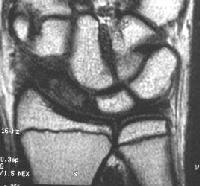

Clinical Example: Scaphoid fracture with total avascular necrosis similar to Preiser's disease

One of the problems with scaphoid fractures is ischemia of the proximal fracture fragment resulting in delayed union, nonunion or irretrievable avascular necrosis. In this case, ischemic changes involving the entire scaphoid are documented following a scaphoid fracture due to minimal trauma. This progressed with cystic changes and AVN on MRI. The patient had persistent pronounced wrist stiffness and pain. As pointed out to me by Dr. Lawrence Schneider (thanks!), this is technically not true Preiser's, for the fracture preceded the AVN.